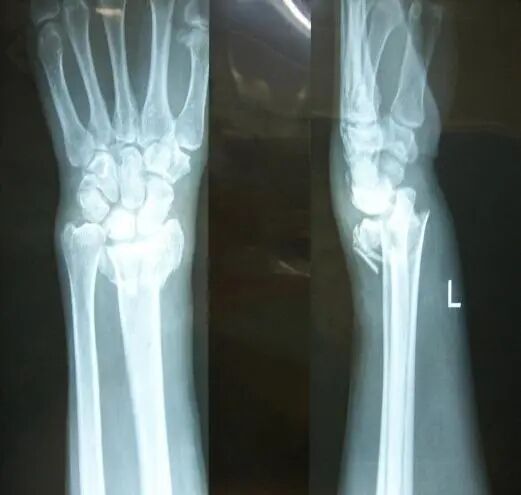

您是否經(jīng)歷過骨折的痛楚?

手術(shù)、住院、難以動彈

花時花費(fèi)花精力。

X線攝片只有在骨量減少達(dá)到30%以上后,才能通過X射線檢查出來,對于早期骨質(zhì)疏松癥狀很難發(fā)現(xiàn)。而該儀器對于診斷骨質(zhì)疏松、評估骨折風(fēng)險及骨質(zhì)疏松治療效果能得到精確評價。